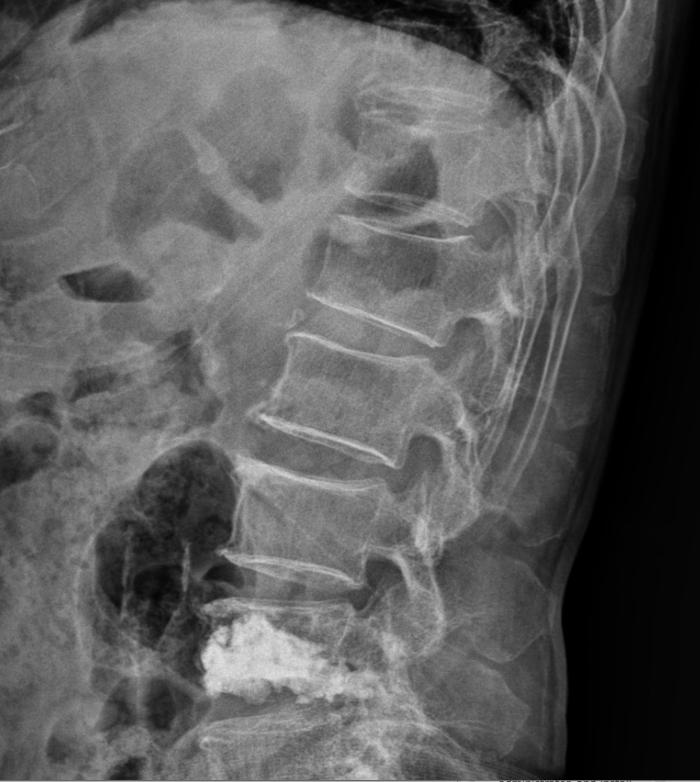

위 와는 다르게 아래의 환자는 골시멘트를 주입하여 압박이 더 되지 않게 척추체를 성형하는 수술과

2.png 이미지